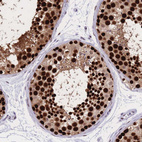

Immunohistochemical staining of human gastrointestinal, lymphoid tissues, pancreas and testis using Anti-NASP antibody HPA030520 (A) shows similar protein distribution across tissues to independent antibody HPA028136 (B).